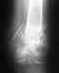

Я из Брянска 38 лет.Огромное спасибо за ответ!Все таки меня меня беспокоит вопрос после введения более толстого гвоздя кость срастется?, притянется ли осколок? и через сколько,он ведь далеко,надо ли вскрывать место перелома для фиксации осколков при сверлении и вводе гвоздя? изначально вскрывали ,и если не сросся меж вертельный перелом,как вверху динамически и с компрессией закрепить гвоздь?Сколько будет стоить такая операция? можно ли пока обойтись,только удалением нижнего болта или это не создаст нужную компрессию. С уважением Дмитрий.

После реостеосинтез с рассверливанием обычно срастается. Про осколок думать не надо, пусть остается, где есть. Должно срастись хотя бы по передней поверхности. С гвоздем внутри запас времени будет очень большой, риск повторного перелома из-за асимметричного сращения отсуствует.

Про "изначально вскрывали" Вы забыли упомянуть в первом сообщении, тогда понятнее, откуда проблемы. Надо делать остеосинтез закрыто, без обнажения отломков, это позволяет максимально сохранить их кровоснабжение.

Удаление нижнего винта вряд ли тут решит проблему, он и так не сильно что-то держит. Тут еще можно было бы подумать про введение винтов вплотную к гвоздю для искусственного сужения канала. Но надежнее поменять гвоздь, поверьте.

Если не сросся вертельный перелом, это даже хорошо, т.к. можно было бы исправить положение и там. Вы показали только одну проекцию, полноценно оценить сращение не получится.